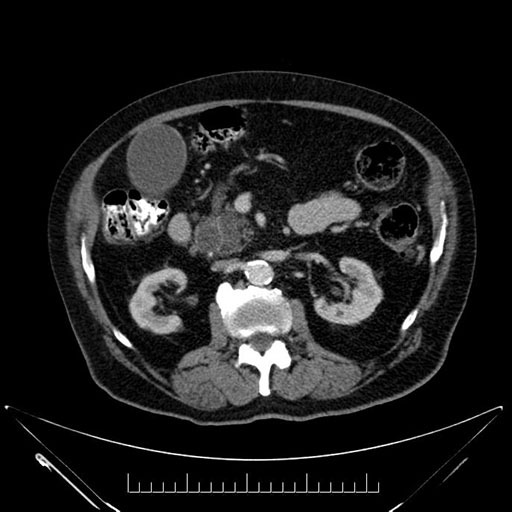

Imaging Analysis

Look through the patient's CT scan to identify any areas of concern for the necessary procedure.

Based on your CT findings, which issue(s) would give reason for "planned slowing down moment(s)" in this case?

Considering a standard Whipple procedure, what step(s) of the operation would you do differently in this case?